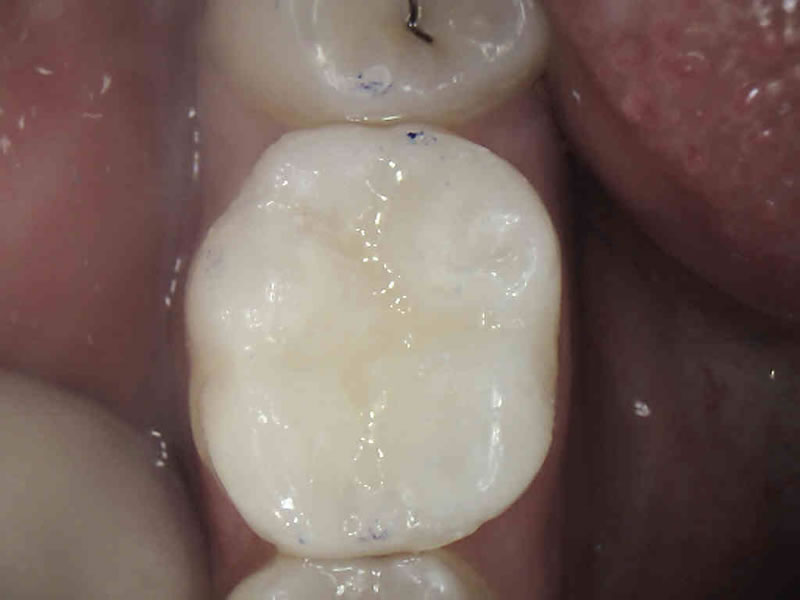

Postavljanjem estetskog materijala postižemo kvalitetnu rekonstrukciju zubnog tkiva i potpuno prirodan izgled za razliku od ( sivog, metalnog ) amalgamskog ispuna.

Za izradu estetskog ispuna potrebno je odstraniti samo bolestan dio zuba za razliku od amalgamskog ispuna za koji je bilo potrebno odstraniti i dio zdravog zubnog tkiva zbog držanja amalgama u zubu.